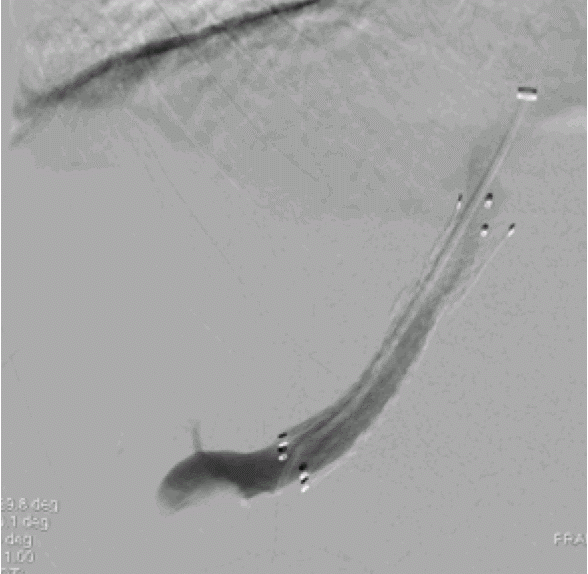

Basics and newer interventions with hands-on workshop